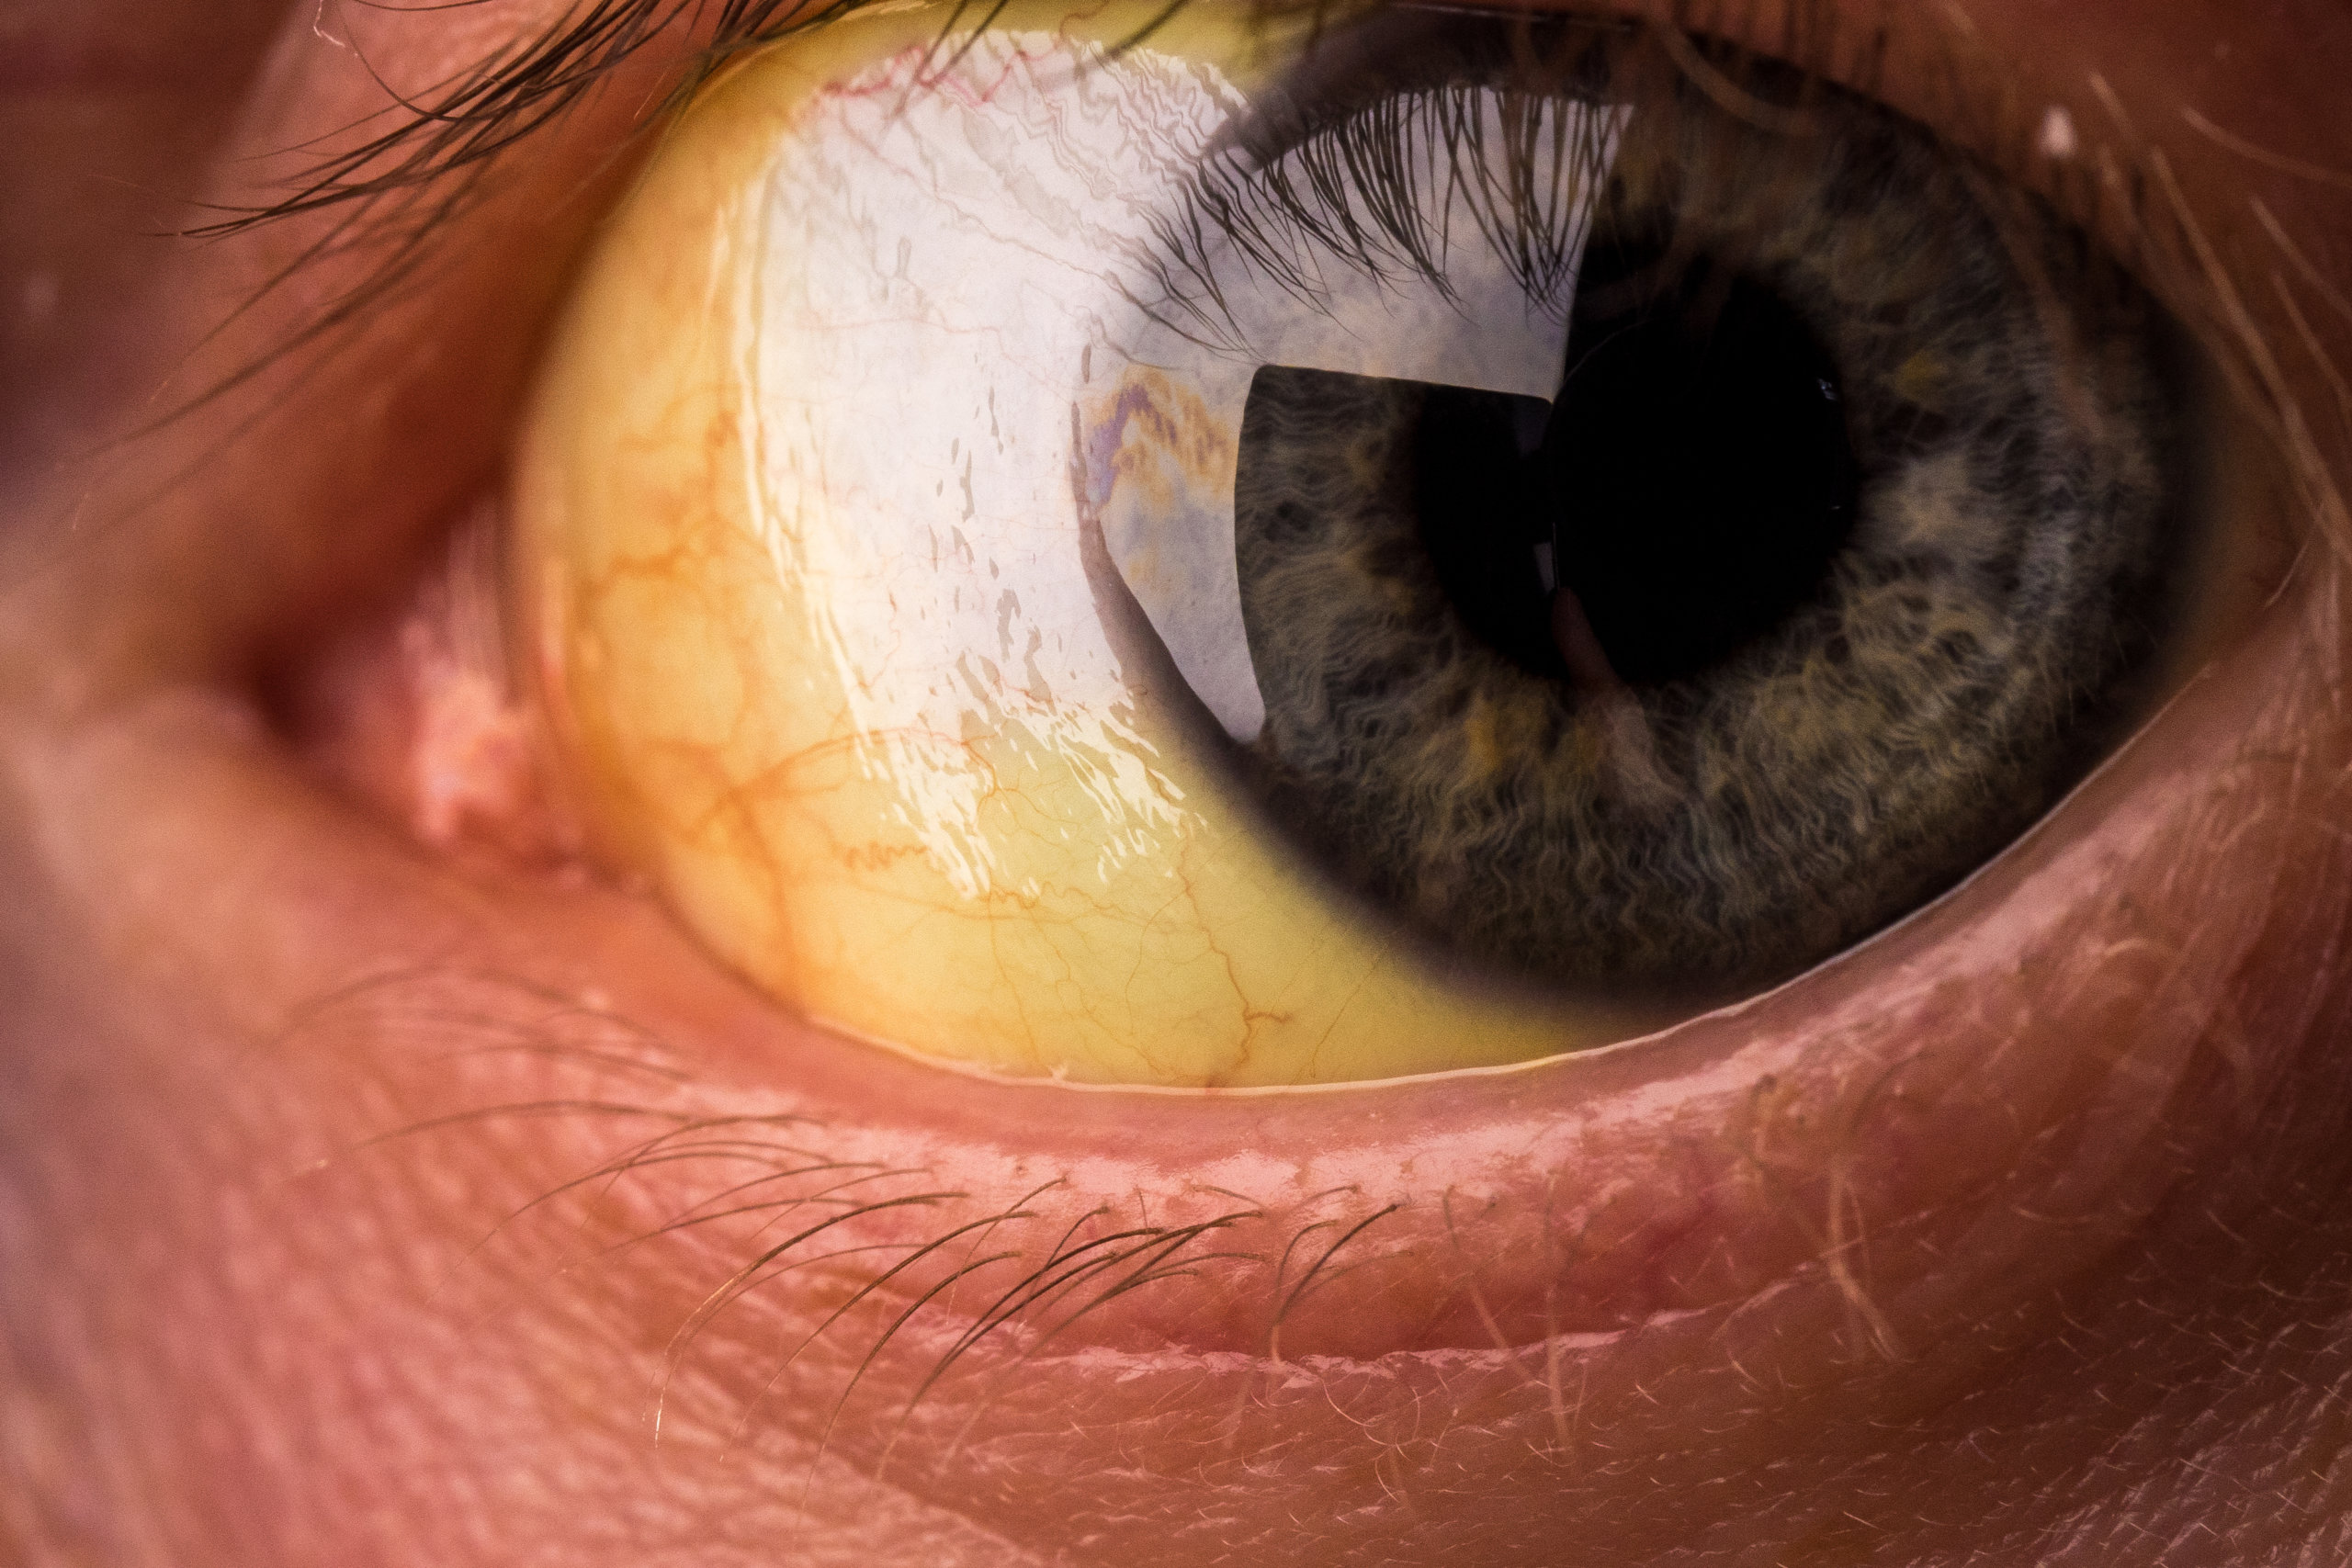

• Jaundice